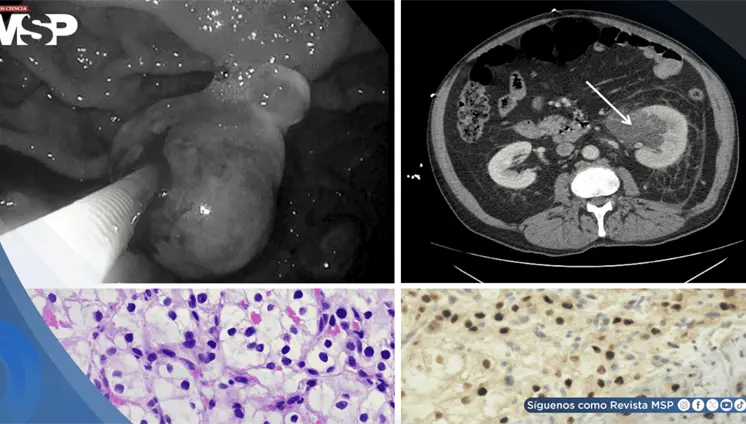

Lo que comenzó como un cuadro frecuente de dolor pélvico y dismenorrea en una mujer, terminó siendo un carcinoma folicular originado en estruma ovárico maligno. La paciente tenía solo 35 años, marcadores tumorales completamente normales y ninguna alteración tiroidea.

La pseudomelanosis vesical es una entidad extremadamente infrecuente, caracterizada por el depósito de pigmento de melanina en el urotelio y macrófagos de la lámina propia.